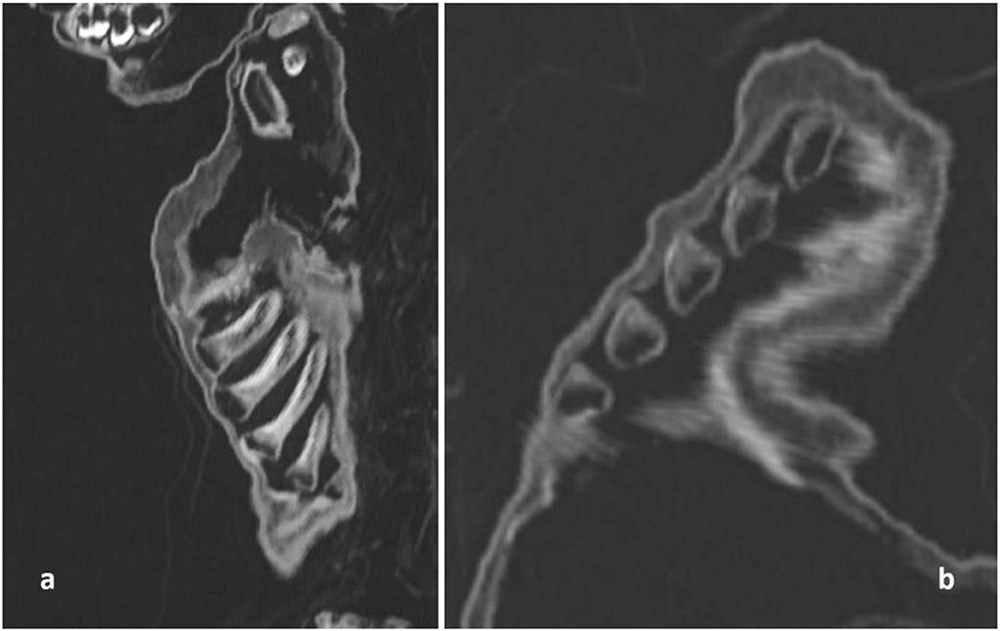

Araştırmacılar, vücudun kemiklerinin oluşumunu ve uzunluğunu ve ayrıca diş patlamasının kanıtlarını inceleyerek, çocuğun öldüğünde yaklaşık bir yaşında olduğunu tahmin edebildiler. Kemikler ayrıca, çocuğun iyi beslenmesine rağmen bozuk kaburgalarında raşitik tespih belirtileri bulundu. Bu durum, raşitizm (D vitamini) ve iskorbüt (C vitamini) gibi spesifik vitamin eksiklikleri ile ilişkili hastalıklardan kaynaklanır.

Akciğerlerdeki iltihaplanma kanıtlarına bakılırsa, çocuk zatürreden ölmüş gibi görünüyor. Rickets’in çocukları zatürreye karşı daha savunmasız hale getirdiği biliniyor. Bu, ne yazık ki çocuğun yetersiz beslenmesinin yanı sıra bu durumun da onun zamansız ölümüne yol açmış olabileceğini düşündürüyor.